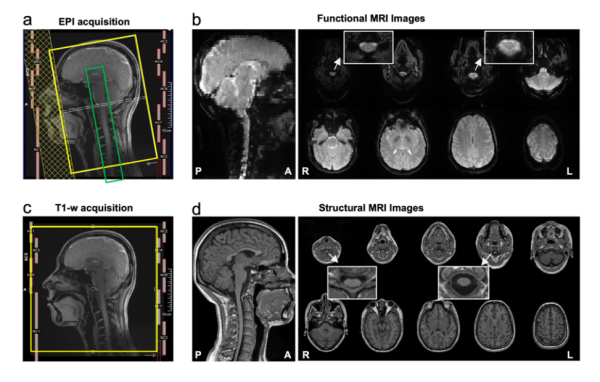

CoSpine成像方案实现了覆盖大脑、脑干、小脑及颈段脊髓的单视野同步采集。这一方案融合多频带并行采集与并行重建算法,可保持1.5毫米高空间分辨率,提升了时间采样效率与图像质量。该策略使皮层-脑干-脊髓神经信号得以在一次扫描中连续获取,为脑–脊髓功能交互研究奠定了方法学基础。

在成像方法之外,研究还构建了基于本成像方案的数据预处理与统计分析框架,实现了数据采集、预处理到标准化配准的系统化优化流程。该流程整合国际主流软件包,并针对脊髓解剖结构的特殊性进行多项算法优化。研究结合呼吸与心跳信号的实时记录,利用生理噪声建模方法实现多层去噪,提升了信号的稳定性。同时,针对脑干和脊髓易受磁场不均影响的问题,方案引入局部匀场优化与反向相位B₀校正策略,减少了几何形变和信号丢失。研究显示,经预处理后的图像信噪比显著提升。

CoSpine功能与结构成像的采集方案及示意图